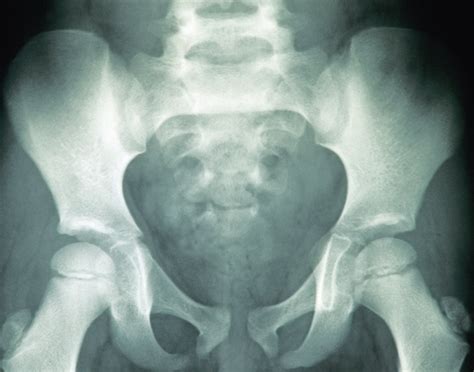

Normal Hip X Rays are a type of radiographic imaging used to visualize the hip joint and surrounding structures. This non-invasive procedure helps diagnose a wide range of conditions, including fractures, dislocations, arthritis, and developmental issues. The hip joint is a complex structure composed of the femoral head, acetabulum, and supporting ligaments and muscles. Normal Hip X Rays provide a clear view of these components, aiding in accurate diagnosis and treatment planning.

Interpreting Normal Hip X Rays requires a trained eye and a thorough understanding of hip anatomy. Radiologists look for specific features and measurements to determine the health of the hip joint. Key areas of focus include:

• Bone Density: Normal bone density indicates healthy bone structure. Any areas of decreased density may suggest osteoporosis or other bone diseases.

• Joint Space: The space between the femoral head and the acetabulum should be uniform and well-defined. Narrowing of this space can indicate arthritis or other degenerative conditions.

• Alignment: Proper alignment of the femoral head within the acetabulum is crucial. Misalignment can suggest dislocations, fractures, or developmental issues.

• Soft Tissue: While X-rays primarily focus on bone structures, they can also reveal abnormalities in soft tissues, such as swelling or calcification.